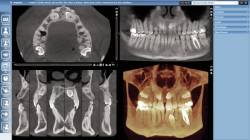

3D Образна диагностика

Planmeca PROMAX 3D е подходящ за множество диагностични изисквания: тези на ендодонтията, пародонта,

ортодонтия, имплантология, лицево-челюстната хирургия и анализ на Темперомандибуларна става. Системата

има софтуер и технология за изследване на синуси, средно ухо, череп, челюсти.

Рентгенов апарат на Planmeca ProMax® 3D отговаря на множество диагностични изисквания и осигурява обемни

размери за всяко клинично приложение.

Planmeca ProMax 3D изображения с размер на средния обем:

Предимството на този метод е, че при изследването на синуси и челюсти, наличните метални

коронки,

мостове и импланти не влошават качеството на получените изображения.

Получените резултати автоматично се визуализират в 3D режим с висока резолюция. Самото

изследване

протича много по-лесно за пациента в сравнение със стандартните КТ изследвания, защото пациентът

не ляга

на маса и не влиза в пръстен, а е в седнало или изправено положение, каторамото на апарата се

върти

около главата на пациента. Това е много важно за пациенти с клаустрофобия.